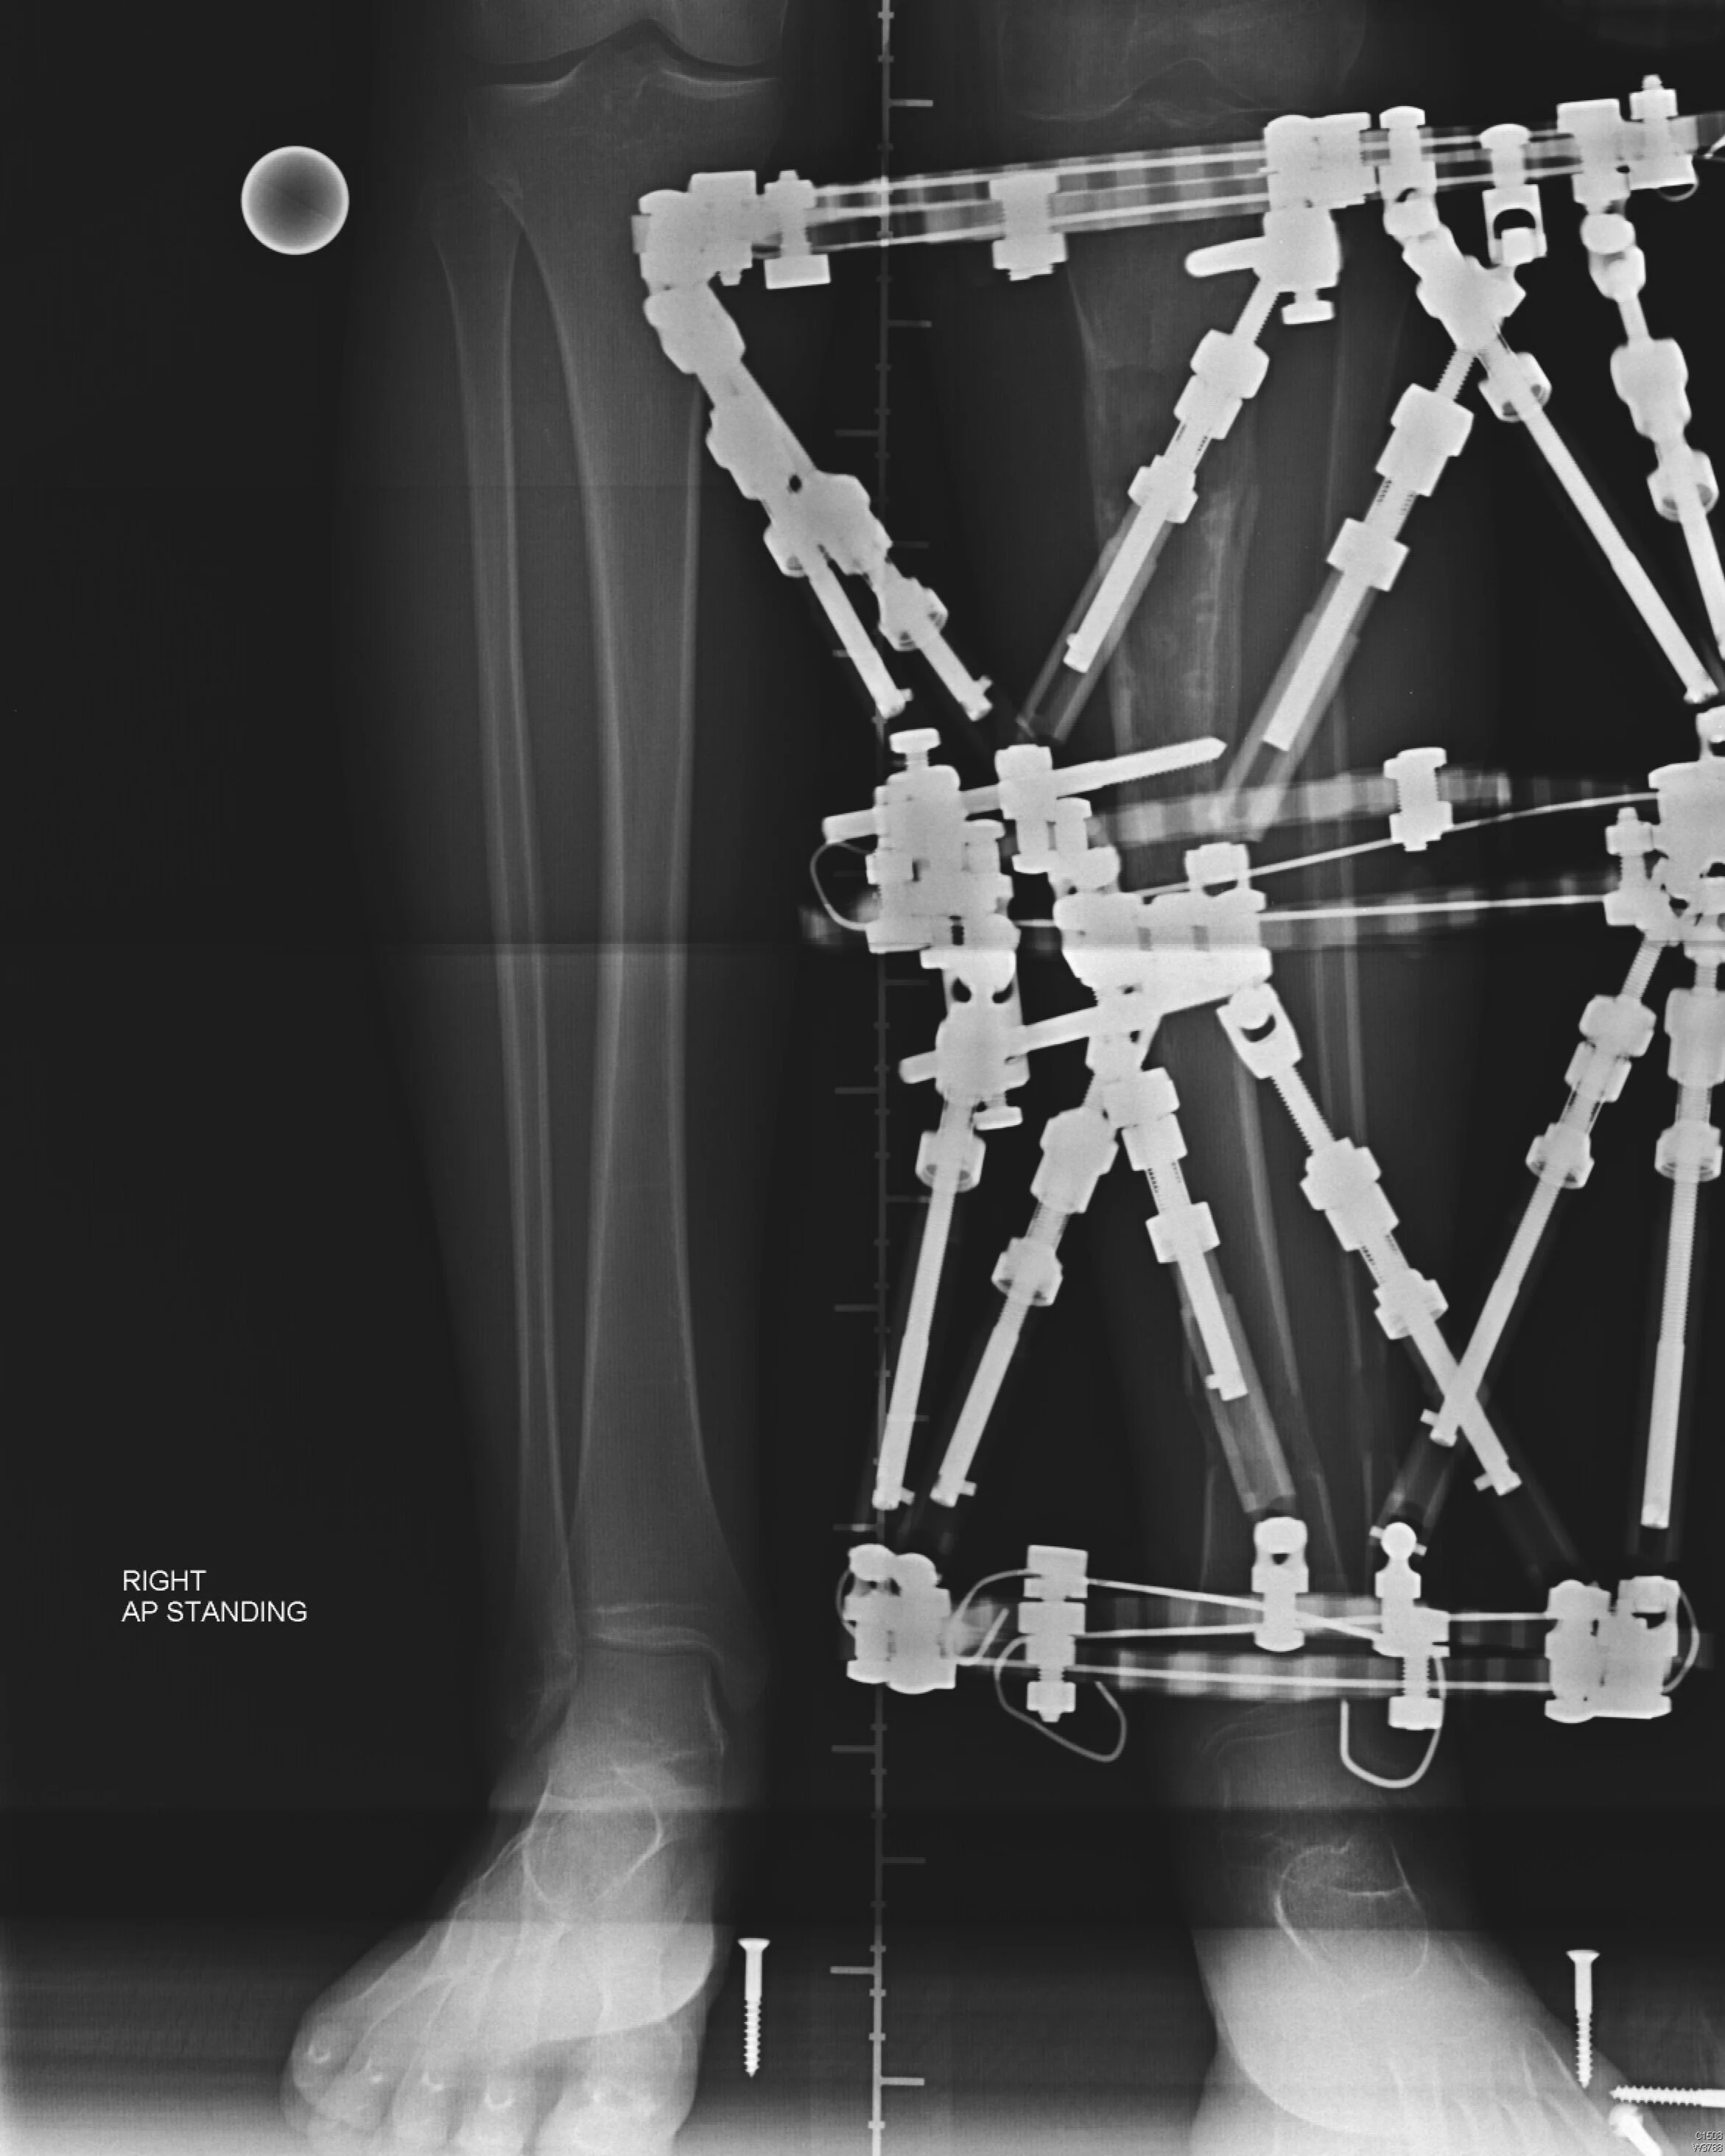

A circular external fixator being used to correct deformities at two places in a tibia, simultaneously.

External Fixator Frame Correction

This has been the mainstay method for bone lengthening using special external fixator frames. The bone is divided and then by turning components on the frame the length and any deformity is corrected over a period of several weeks. This treatment is highly specialised and time consuming but excellent results can be achieved. The main complications relate to pin infections which do not occur with the new nails. Frames will still have a role in younger children who are too small to be fitted with a lengthening nail.